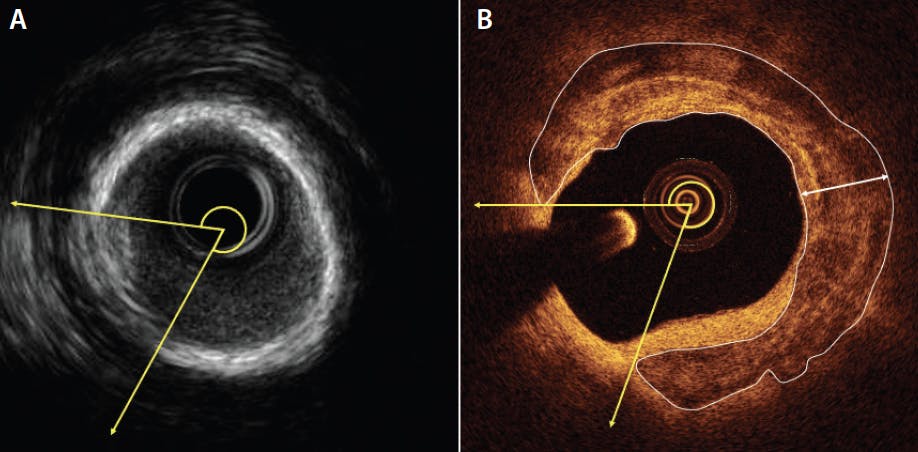

Extensive calcification of the target lesion is an important determinant of stent underexpansion, which is a predictor of subacute and late adverse events. IVUS is sensitive in detecting calcium, but because ultrasound cannot penetrate calcium, quantifications derived from IVUS are limited to the circumferential distribution of calcium and its longitudinal length. Calcium depth is visually determined as superficial (close to the lumen) or deep (away from the lumen). Conversely, infrared light can penetrate calcium. Therefore, OCT allows more accurate quantifications of coronary calcification, such as circumferential distribution, longitudinal length, calcium thickness, calcium area, and distance from the lumen (Figure 1).

Figure 1. Quantification of coronary calcification. IVUS image of a circumferential and superficial calcification (A). An OCT image of a circumferential calcification (B). As infrared light travels through calcium, it is possible to quantify the calcium area, the calcification thickness (double arrowhead points to the thickest portion), and the distance from the lumen. Opposite to previous knowledge, this superficial and circumferential calcification, with a maximum thickness of 460 mm, can be easily fractured with noncompliant balloon inflation.